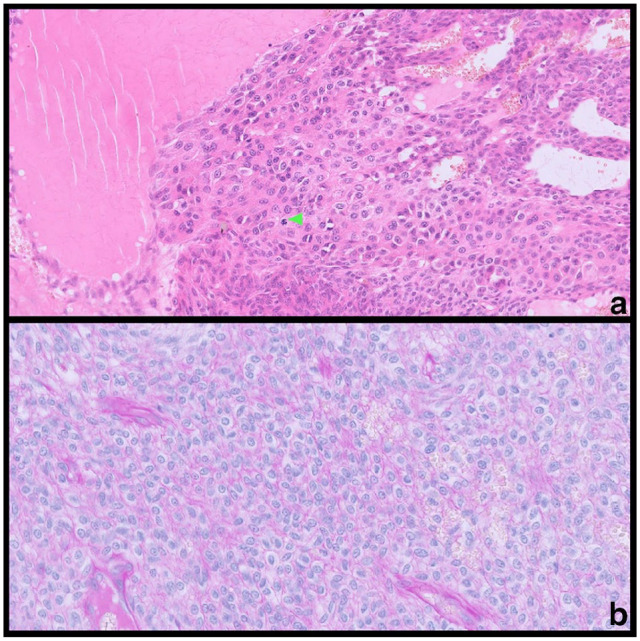

Case summaryA 4-year-old male castrated domestic shorthair cat presented with a 2 cm painful cutaneous mass on its right lateral abdominal wall. The cat inflicted self-trauma to the lesion site causing secondary ulceration and mild haemorrhage. Fine-needle aspiration or incisional biopsy was advised, along with diagnostic imaging; however, excisional biopsy was preferred by the owners. The mass was surgically removed with 1 cm lateral margins and a deep fascial plane. The histopathological features were most consistent with a diagnosis of a glomus tumour; the diagnosis was supported by subsequent immunohistochemistry. The tumour was completely removed and there were no signs of recurrence at the 6-month follow-up. In this case, surgery is expected to be curative. Relevance and novel information To the authors' knowledge, this is the first report of a glomus tumour of the body wall in a cat and its association with pain and self-trauma. This report aims to add more data to the diagnosis and presentation of glomus tumours in animals.